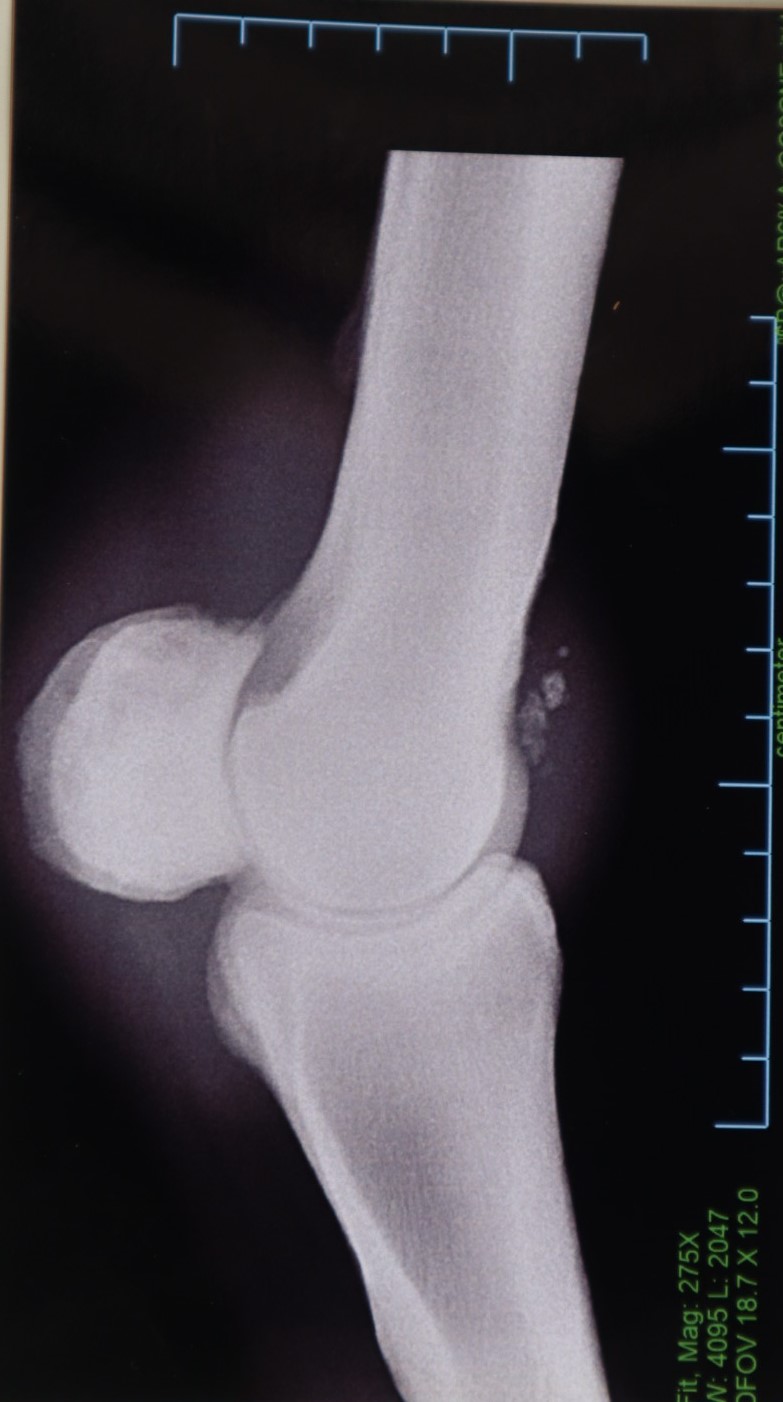

本馬は船橋・佐藤裕太厩舎より2歳9月にデビュー。2戦連続して2着となった後の3戦目に待望の初勝利を挙げます。ところが、両前の橈骨遠位端を剥離骨折するアクシデント。約1年に及ぶ長期休養に入ります。

今年に入っては心機一転、川崎競馬の現厩舎に移籍して実戦復帰。復帰3戦目に7勝目を挙げています。なお、今週の3回川崎開催(6/12~)での出走を目標にペースアップを図っていたところ、左前球節骨膜剥離が判明。残念ながら、今回の出品に至りました。

左前球節の骨膜剥離について『保存療法で対処できるレベルではあるものの、手術を行ってあげることに越したことはありません。いずれにしても、全治まで6~9ヵ月程度を要するでしょう』との診断を受けています。昨年、左前球節のトラブルで休養しており、その際の骨膜がこのタイミングではがれてしまったようです。前厩舎時代にも骨折した経緯があることを踏まえても、常に骨質の問題を抱えていたことでしょう。現B2クラスでも勝ち負けの目処が立ち、さらなる活躍が期待できていただけに残念です。(川崎競馬・鈴木義久調教師)

※2023年6月の調教中に左前球節骨膜剥離を発症しています。

※2019年12月11日(2歳時)の競走中に左前橈骨遠位端剥離骨折を発症。右前橈骨遠位端剥離骨折も判明したため、同月23日に両前の骨片摘出手術およびクリーニング手術を行っています。